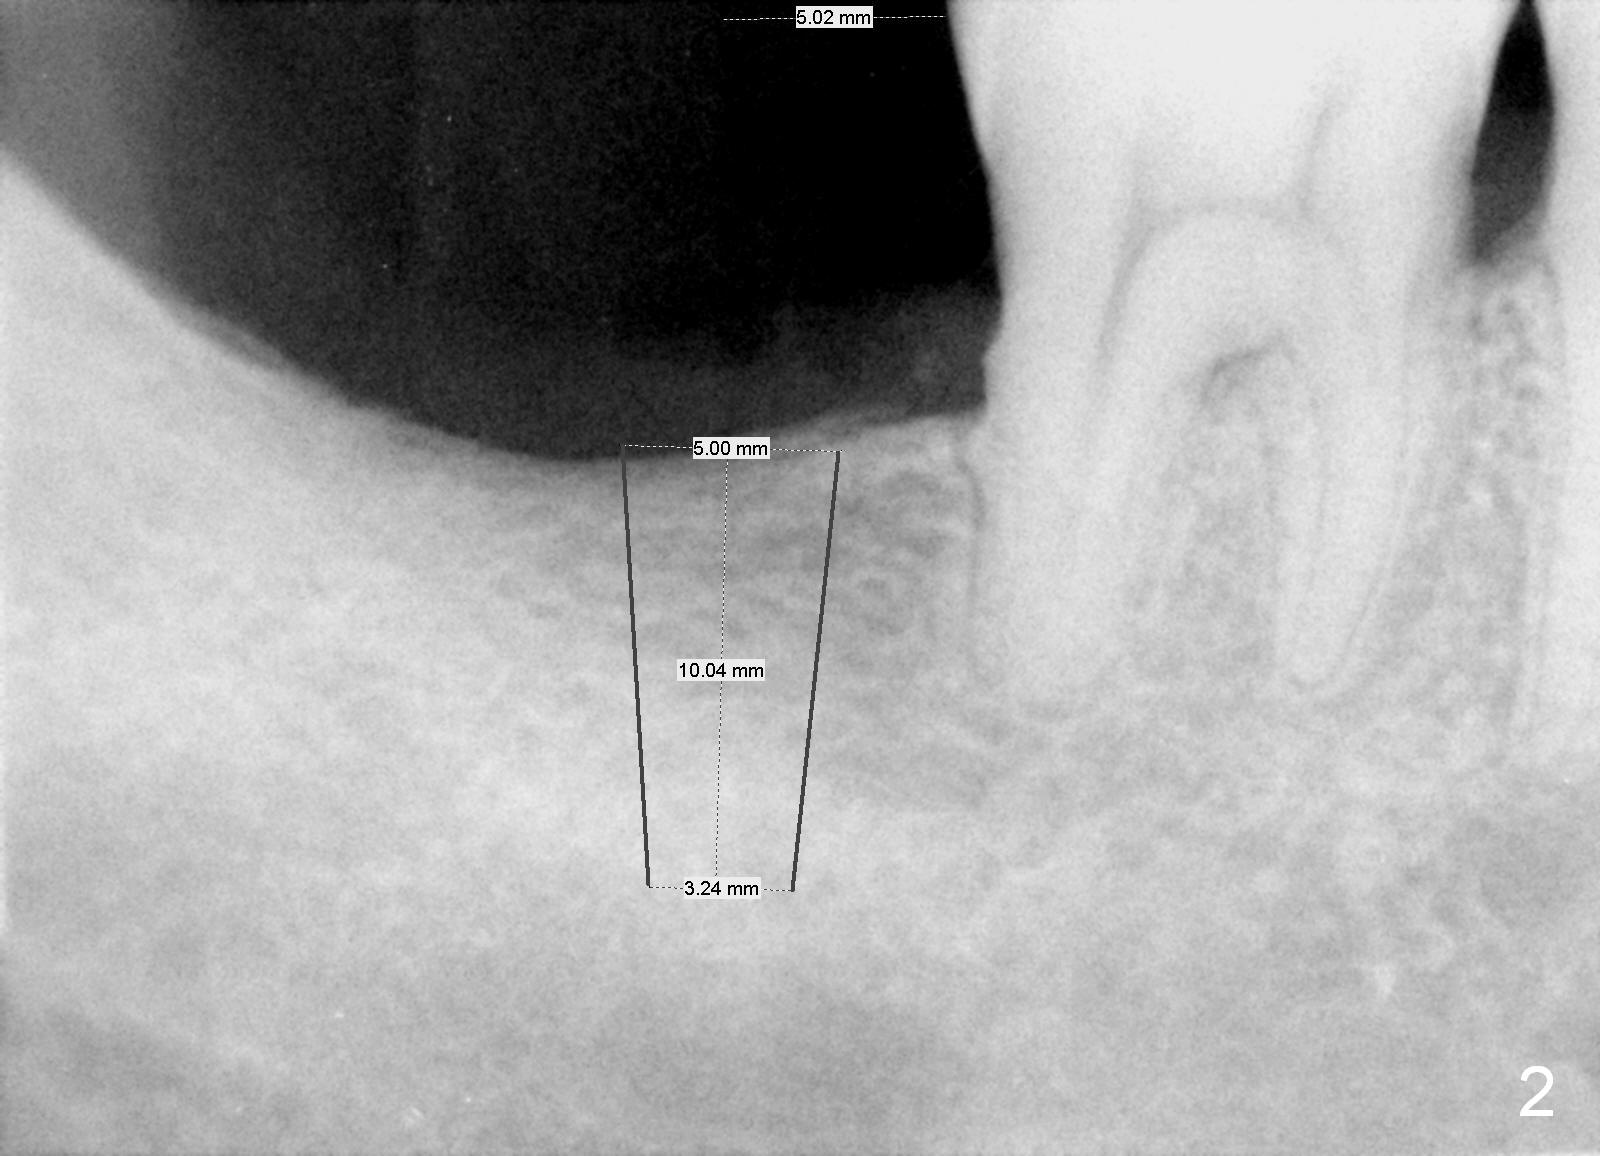

Limited Bone Height with Indistinct Inferior Alveolar Canal

A 45-year-old man has lost the tooth #31 for several years. The Inferior Alveolar Canal is indistinct (Fig.1,2). Although the bone height is more than 10 mm, the initial osteotomy depth is 8 mm. It is also easy to change trajectory with short osteotomy. Use 4 mm implant spacer to position the starter drill.